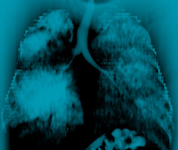

Злокачественная эндобронхиальная обструкция на мультидетекторной КТ: корональная реконструкция, демонстрирующая злокачественную обструкцию правого главного бронха

Из коллекций Хосе Фернандо Сантакруза, дипломированного врача, члена Американской коллегии специалистов в области торакальной медицины, DAABIP, и Эрика Фолка, дипломированного врача, магистра наук; используется с разрешения